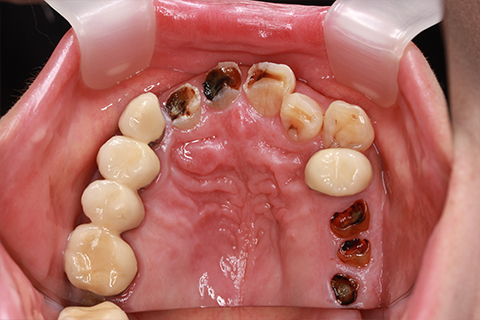

症例5

- 年齢・性別

- 35歳男性

- 治療期間

- 3ヶ月

- 抜歯

- 右上1.3左上6.7の残根抜歯

- 治療費

- 132万円

- 備考

- 右上1.3左上6.7の欠損部

- 治療内容

- 4本のインプラントを一回のオペで埋入。

- 施術の副作用(リスク)

- オペによる知覚障害。インプラントによる歯肉炎。インプラント脱落。